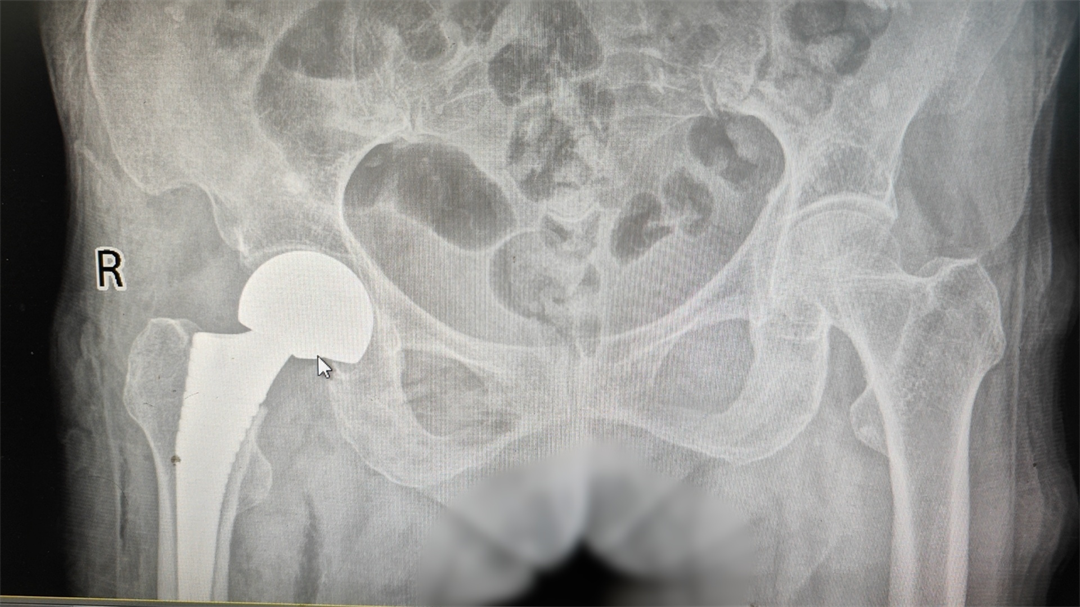

患者術(shù)后影像資料

手術(shù)歷時(shí)半小時(shí),切口約5-6cm,術(shù)中出血40ml,術(shù)后假體位置良好,生命體征平穩(wěn),安全返回病房。

髖關(guān)節(jié)置換術(shù)示例圖

髖關(guān)節(jié)置換是骨科常見的手術(shù)治療方式,是一種以人工假體置換病變髖關(guān)節(jié)的手術(shù)治療過程,是治療晚期髖關(guān)節(jié)疾病及股骨頸骨折的有效手段。